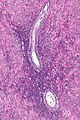

Ablated_endometrium. H&E stain. | |

| LM | endometrium completely or partially replaced by hyaline material and fibrosis |

- Endometrium completely or partially replaced by:

- Hyaline material, fibrosis.

UTERUS, UTERINE CERVIX, TOTAL HYSTERECTOMY: - SUPERFICIAL FIBROSIS AND HYALINE CHANGE OF THE UTERINE LINING -- COMPATIBLE WITH PRIOR ABLATION. - UTERUS WITH LEIOMYOMAS. - UTERINE CERVIX WITHIN NORMAL LIMITS.